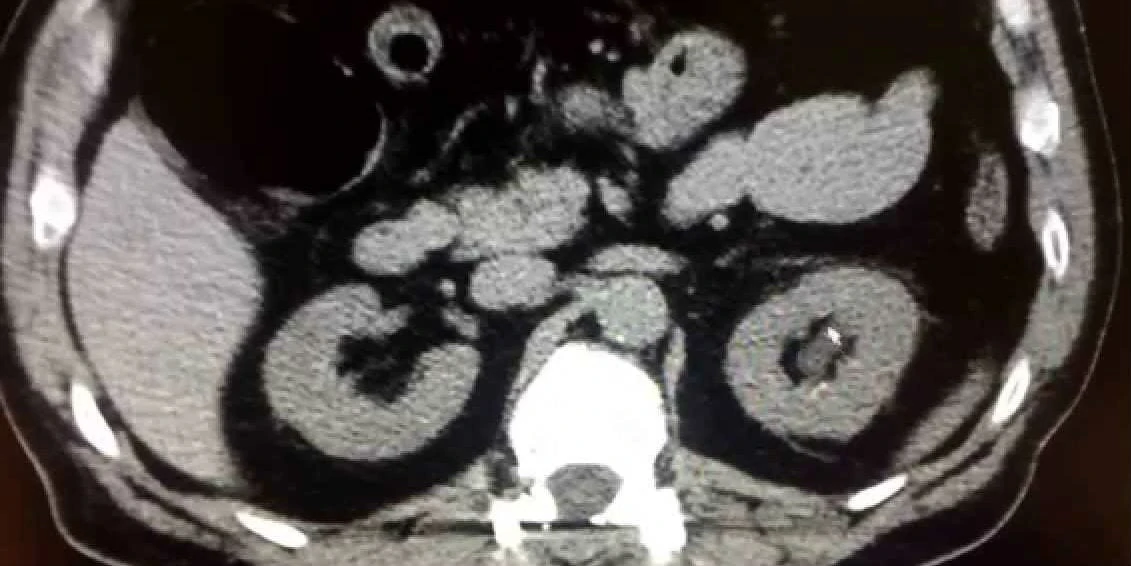

Ce qu’il faut savoir, c’est qu’Alex n’a qu’un seul rein, résultat d’un problème survenu peu de temps après sa naissance. C’est la seule partie du corps qui lui manque… et c’est évidemment celle qui est attaquée.

Après plusieurs scans sans résultats concluants, Alex est mis devant un dilemme important: vivre avec la masse ou la faire enlever.

Dans la présente situation, rien n’est noir ou blanc. Si une biopsie est faite, ça pourrait aggraver son cas si la masse est maligne. Si la biopsie révèle une masse bénigne, il y a 20% des chances que le résultat ne soit pas valide.

Et c’est encore moins rassurant quand on n’a qu’un rein.

Le chirurgien d’Alex décide d’en parler à 4 autres collègues. Des sommités. Les 2 premiers sont catégoriques: « Parce qu’il est jeune, en bonne forme physique et en santé, on ne touche à rien et on fait des suivis constants ». Les deux autres, eux aussi, sont catégoriques : « Parce qu’il est jeune, en bonne forme physique et en santé, on enlève la masse sur le rein. »